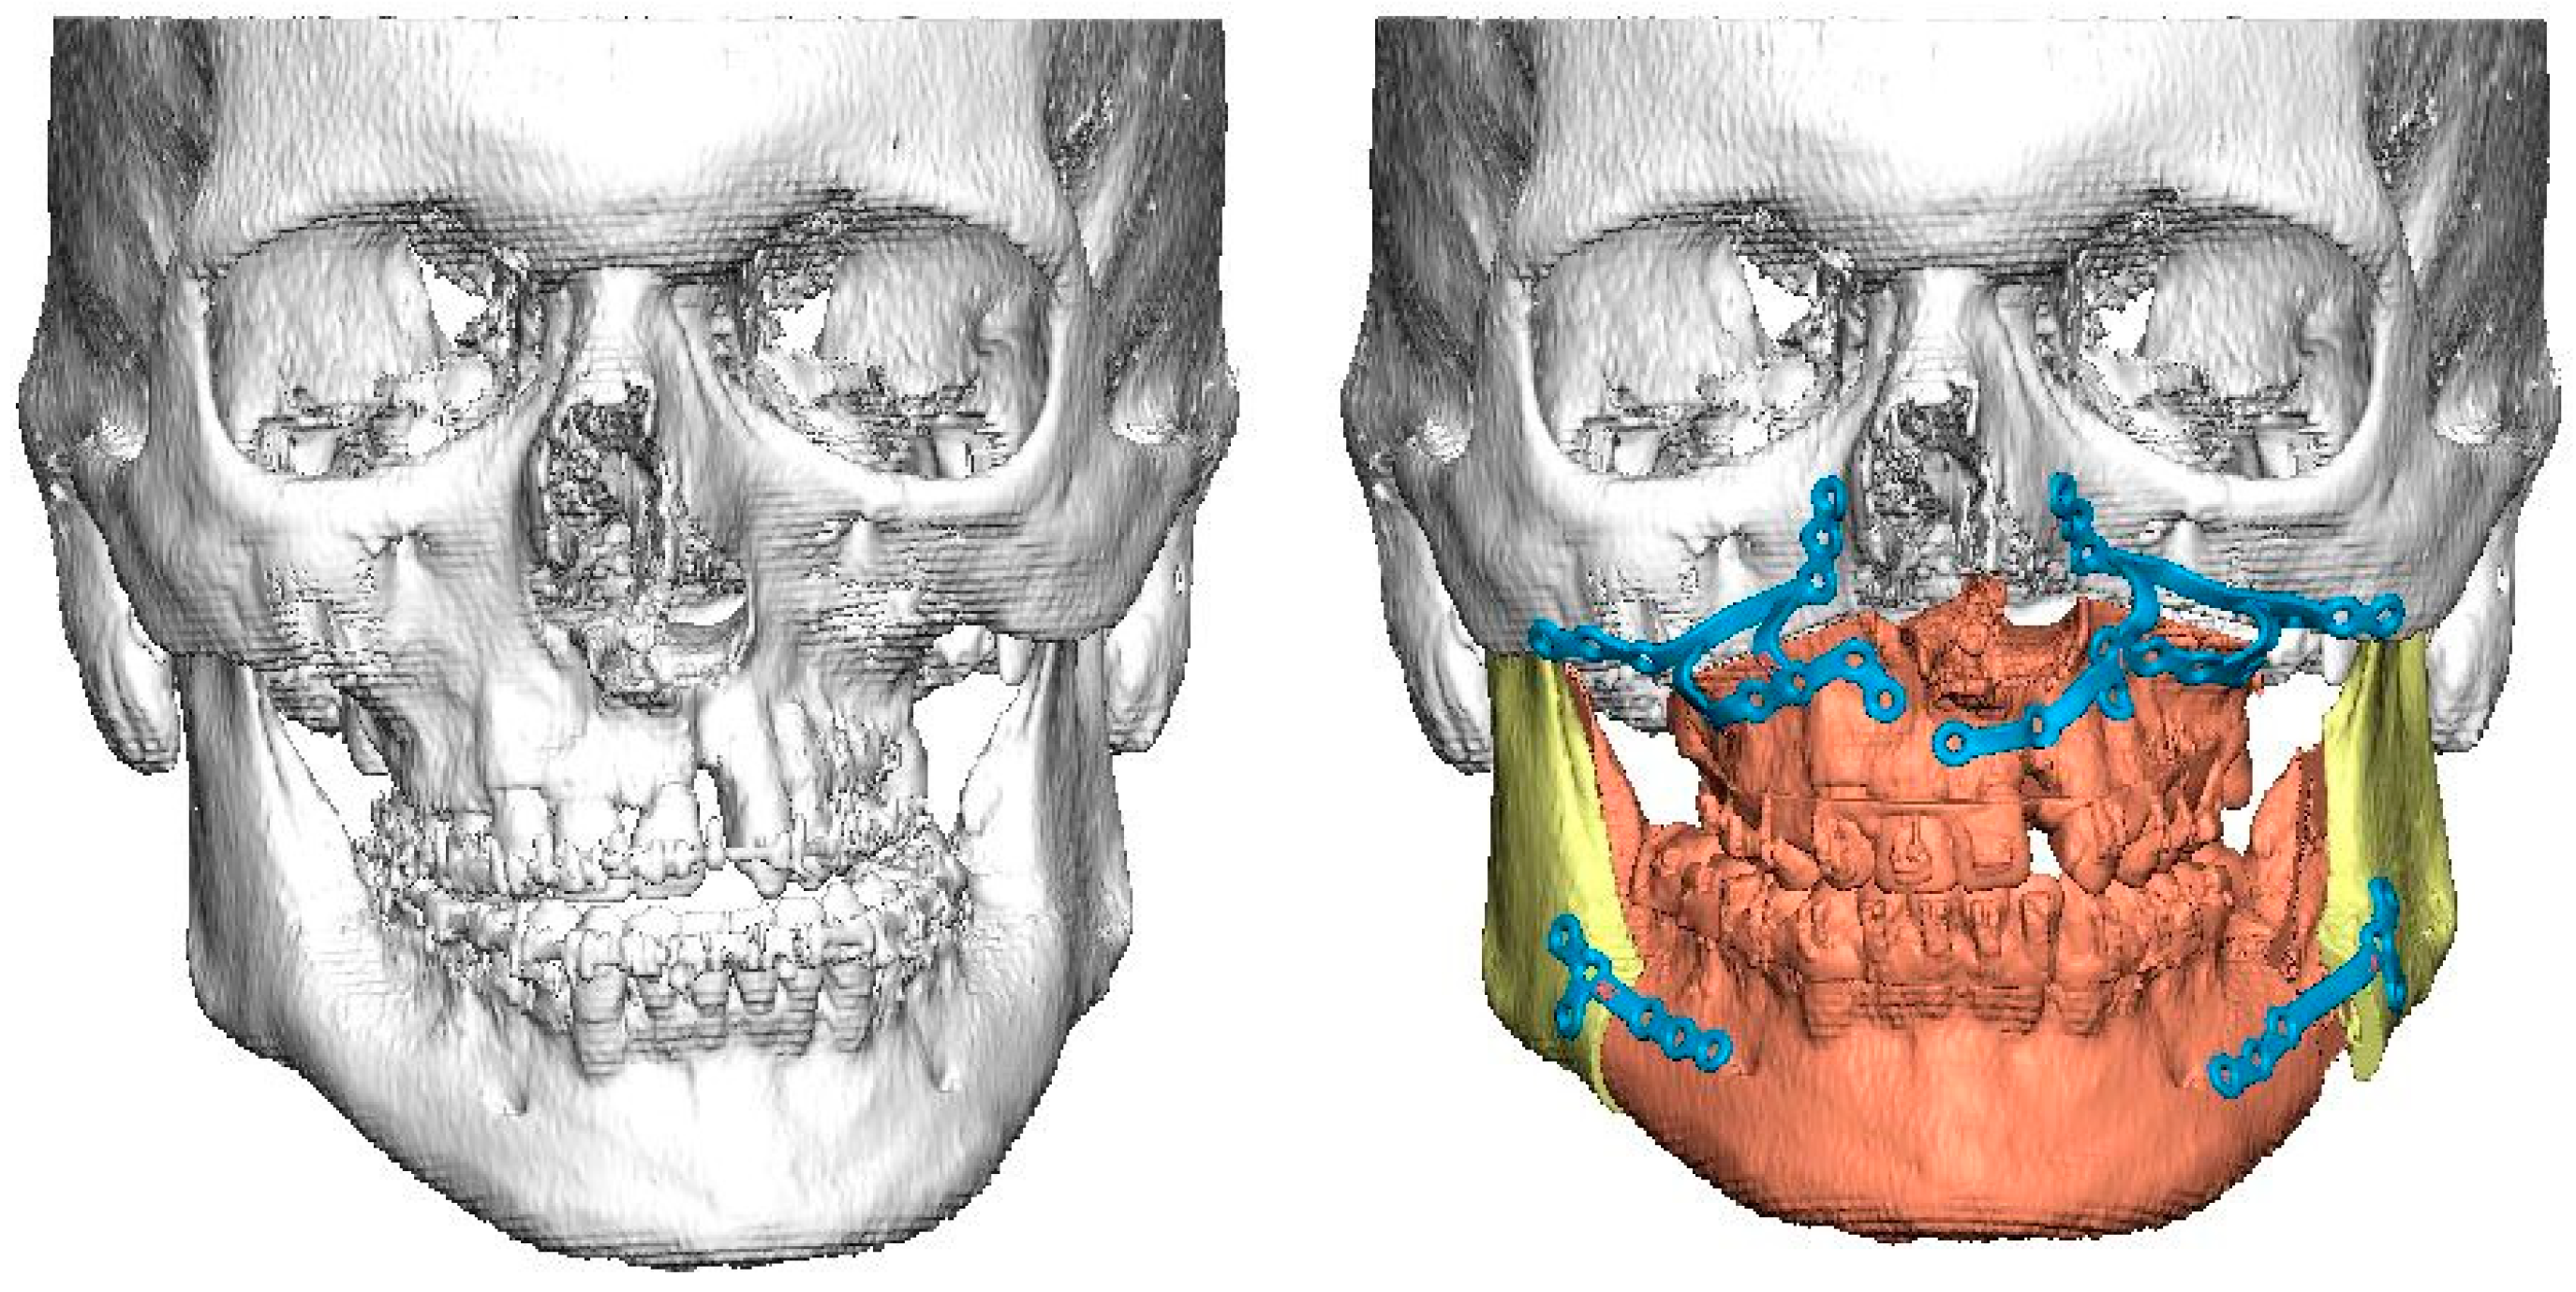

To assess the size of the rim of bony orbit, the width and height were measured from the most anterior CBCT or CT slice showing the whole orbital rim (Figure 2A), and the depth was the distance from the frontozygomatic suture to the optic canal (Figure 2B). The position of bony orbit was assessed as the distance of the cranio-lateral border of the infraorbital canal opening to the inner postero-caudal wall of the sella turcica, measured from an oblique sagittal plane (Figure 2C). Helsinki University Hospital radiologist workstations and Syngo software (Siemens Healthineers, Erlangen Germany) were used for the analysis according to the manufacturer’s instructions for quantitative analysis. The volume of bony orbit was measured with semi-automated segmentation to avoid potential measurement-related bias since the cleft side is always visible to the radiologist in the lower sections during the orbital analysis. Semi-automated orbital volume analysis was performed using CMF Orbital Software (Disior Ltd., Helsinki, Finland). To use the software, the radiologist only selects a seed point inside the orbital vault and confirms the side to be examined. The apex of the orbit at the conjunction of the optic nerve and bulbus was used as a seed point in all cases. After selecting the seed point, the virtual program-generated triangle mesh iteratively expands from the starting position until it meets the bony walls of the orbit. The anterior expansion of the volume mesh network automatically stops when the mesh reaches the bony rim of the orbit (Figure 3). This system is described in more detail, and the reliability of the software measurements is proven to be high (0.992 (95% CI 0.987–0.997 intraobserver ICC and 0.989 (95% CI 0.983–0.993)) interobserver ICC in intact orbit) [25]. All volume analyses and the surface reliability of the software algorithm were confirmed by the radiologist in all cases. All the measures of the cleft patients were made by the same radiologist (E.P.).

Figure 2.

(A) The width and height of the bony orbit from the most anterior CBCT or CT slice showing the whole orbital rim. (B) The depth from the frontozygomatic suture to the optic canal opening. (C) The position of bony orbit was assessed as the distance of the cranio-lateral border of the infraorbital canal opening to the inner posterocaudal wall of sella turcica, measured from an oblique sagittal plane.